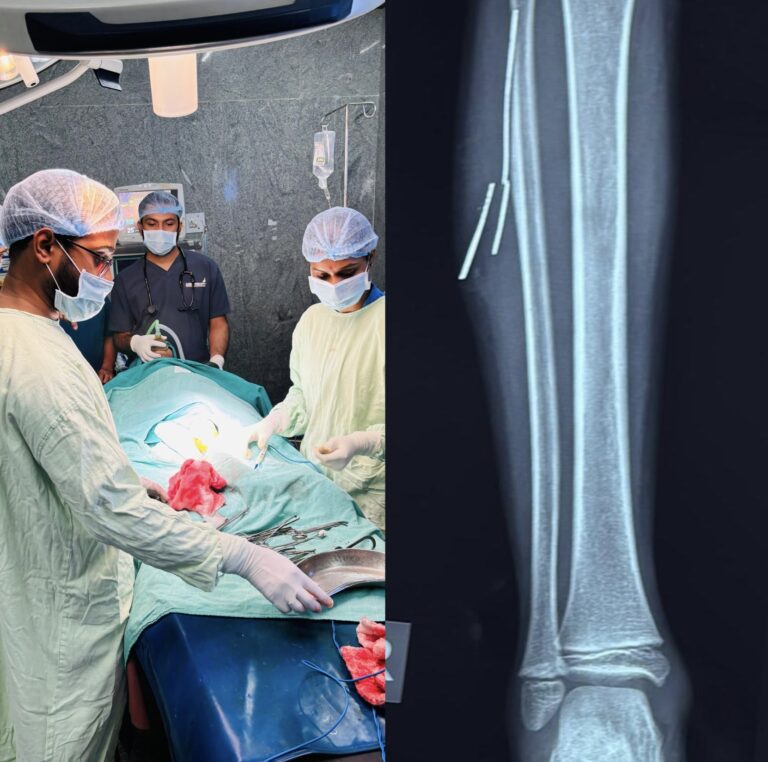

बिलासपुर [जनहित न्यूज़]सिम्स (छत्तीसगढ़ आयुर्विज्ञान संस्थान) बिलासपुर ने एक बार फिर अपनी चिकित्सकीय दक्षता और तकनीकी संसाधनों...